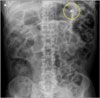

An abdominal radiograph showed what appeared to be a small light bulb in the left upper quadrant (A). This study was compared with a film of the same patient obtained 3 years earlier that also showed a foreign body (B). There was no mention of this object in the accompanying radiology report. A CT scan of the abdomen revealed a metallic foreign body (about 2.3 x 1.2 cm) in the region of the descending portion of the duodenum.

An upper endoscopy was performed. The foreign body was located in the bulb of the duodenum and was retrieved intact with a basket and overtube (C). The specimen was identified as a broken light bulb (D), with a 1 x 1-cm glass portion and 1.2 x 0.7-cm metallic portion. At follow-up, the patient’s GI symptoms had diminished.